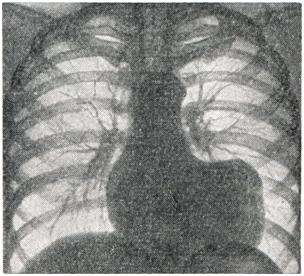

Рентгенодиагностика аневризмы сердца начала развиваться в двадцатых годах 20 в. [Кристиан, Фрик (Н.А. Christian, H.Frick), 1922] и продолжает совершенствоваться, обогащаясь новыми методиками, и. все же распознавание этого заболевания представляет значительные трудности. Для диагностики аневризмы сердца необходима многопроекционная рентгеноскопия с тщательным изучением особенностей сокращений сердца с целью выявления свойственных аневризмам зон акинезии («немых зон») и дискинезии (парадоксальной пульсации). Кроме рентгенограмм в прямой и косых проекциях, рекомендуются рентгенограммы с небольшим поворотом больного (на 20 — 30°) как в правое, так и в левое косое положение. В тех же проекциях производят рентгенокимографию и электрокимографию. Наиболее важным признаком мешковидной аневризмы сердца служит полуовальное выпячивание на контуре левого желудочка (рис. 2 и 3), отграниченное с обеих сторон «зарубками». Для большой аневризмы сердца характерно резкое увеличение поперечника сердечной тени. Левый контур сердца при этом нередко имеет прямоугольные очертания (рис. 4.). Эти грубые морфологические признаки непостоянны и часто отсутствуют при диффузных аневризмах. Поэтому большое значение приобретает симптом волнистости контура, то есть слабо выраженные, иногда едва заметные плоские выпячивания. Роль этих признаков резко возрастает, если соответственно такому выпячиванию наблюдаются и нарушения контрактильных свойств миокарда в виде неподвижности контура или парадоксальной пульсации. Следует учесть, что прослеживание феномена парадоксальной пульсации по заднему контуру левого желудочка во втором косом и боковом положениях может наблюдаться и в норме вследствие систолического преобразования формы сердца. Иногда по контуру левого желудочка видны небольшие углообразные деформации контура (сращения перикарда). В распознавании функциональных признаков аневризмы сердца большое значение имеет рентгеноскопия, но для детального изучения необходима графическая запись движений сердечного контура — рентгенокимография и электрокимография. На рентгенокимограммах отчетливо определяются зоны акинезии, их локализация и протяженность. При сопоставлении рентгенокимограмм аорты и сердца обнаруживаются несвоевременные — парадоксальные (в систоле — кнаружи) смещения контура в области аневризмы сердца, а иногда также признаки резких пассивных смещений истонченной фиброзной стенки аневризмы сердца в виде «оторванных сегментов» сердечной тени или парадоксальной поперечном полосатости сердечной тени (М. А. Иваницкая, 1950). Преимуществом электрокимографии является возможность более точного анализа йарушений контрактильности миокарда: при записи движений контура левого желудочка в области аневризмы сердца определяется подъем кривой во время систолы вместо спуска ее в норме, причем одновременная запись электро- или фонокардиограммы позволяет точно установить время возникновения этого парадоксального движения, продолжительность и амплитуду его по отношению к общей амплитуде кривой. Различают полную парадоксальную пульсацию контуров аневризмы, когда движение в систоле кнаружи занимает всю систолу (это особенно резкие нарушения контрактильности миокарда), и частичную парадоксальную пульсацию, когда это движение занимает лишь часть систолы; при этом зубец как электрокимографической, так и рентгенокимографической кривой приобретает дополнительную вершину. Большое значение для распознавания аневризмы сердца имеет рентгенокимография, обеспечивающая одновременное изучение морфологических и функциональных признаков. Функциональные рентгенологические признаки облегчают диагноз плоских, диффузных аневризм, не дающих выразительном морфологической картины. Для выявления верхушечной аневризмы сердца рекомендуется исследование при глубоком вдохе или с раздуванием желудка. Аневризмы нижней стенки левого желудочка не распознаются при обычном рентгенологическом исследовании. Наиболее точную морфологическую и функциональную характеристику аневризмы сердца в настоящее, время обеспечивает киновентрикулография [Горлин (R. Gorlin), 1967], с помощью которой ныинляются аневризмы любой локализации. Сравнение данных комплексною рентгенологического исследования сердца до и после операции позволяет дать объективную оценку результатам хирургического лечения аневризмы сердца. Использование современных специальных методов исследования позволило повысить частоту прижизненной диагностики аневризмы сердца, что имеет большое практическое значение в связи с успехами хирургического лечения этого заболевания. Аневризма сердца относится к прогностически неблагоприятным осложнениям инфаркта миокарда. Многочисленные отечественные и зарубежные статистики показывают, что спустя 5 лет после инфаркта миокарда, осложненного аневризмой, в живых остаются не более 12% больных. В первые 3 года после инфаркта, осложненного аневризмой, умирают 73%, а через 5 лет — 88% больных, в том числе от сердечной недостаточности — 70% и от тромбоэмболических осложнений — 30%, хотя имеются отдельные указания о продолжительности жизни больных до 10 и более лет. Другими осложнениями, приводящими к смерти больных аневризмой сердца, являются повторные инфаркты и реже — разрывы аневризмы. Поэтому в настоящее, время консервативное лечение следует использовать только для борьбы с осложнениями и как подготовку к операции. Оперативному лечению подлежат: 1) больные с хроническими аневризмами сердца, осложненными сердечной недостаточностью, стенокардией, аритмией, неподдающиеся консервативной терапии; 2) больные с аневризмой сердца, осложненными тромбозом мешка или его прогрессивным увеличением, грозящим разрывом. Только у некотоорых больных с небольшой неосложненной диффузной или мешковидной аневризмой сердца при стабильном состоянии операцию можно отложить при условии диспансерного наблюдения до изменения клинической картины.Резекция мешковидных аневризм сердца должна производиться не ранее чем через 3—4 месяца после перенесенного инфаркта, то есть когда образуется прочная рубцовая ткань, предупреждающая несостоятельность швов по линии иссечения аневризматического мешка. Исключением являются быстро увеличивающиеся аневризма сердца Операция не должна производиться больным с большой диффузной аневризмой сердца при плохой функции оставшейся части желудочка. Относительным противопоказанием к хирургическому лечению аневризмы сердца является возраст больных — старше 65 лет. В связи с тяжелым состоянием больных и сложностью операций вмешательства при аневризме сердца носили до середины 50-х годов 20 в. случайный характер. В 1931 г. Зауэрбрух (Е. F. Sauerbruch) во время операции на грудной клетке по ошибке вскрыл аневризму правого желудочка, принятую им за опухоль средостения, ушил ее у основания и иссек. В 1942 г. Бек (С. S. Beck) укрепил свободным куском широкой фасции бедра стенку постинфарктной аневризмы левого желудочка, диагностированной дооперации. С 1944 г. при хирургическом лечении хронической аневризмы сердца применяется ряд вмешательств: 1) укрепление истонченной стенки аневризмы различными аутотрансплантатами: грудной мышцей [Д'Аллен (С D. Allen), 1956], большим сальником (В. И. Казанский, 1964), кожным лоскутом [Ниднер (F. F. Niedner), 1955] и др.; 2) погружение аневризмы швами (Б. В. Петровский, Ф. Г. Углов, А. А. Вишневский, 1954 — 1957); 3) погружение аневризмы швами с помощью межреберной мышцы на ножке [Шпачек (В. Spacek), 1954]; 4) резекция аневризмы закрытым способом с использованием игольчатого зажима [Бейли (С. P. Bailey), 1954]; 5) резекция аневризмы на открытом сердце в условиях искусственного кровообращения [Кули, Каткарт, Лиллихей (D. A. Cooley, R. Т. Gathcart, С. W. Lillehei), 1958; Б. В. Петровский]; 6) различные варианты диафрагмопластики — укрепление стенки сердца лоскутом диафрагмы (Б. В. Петровский, 1957). Операция укрепления стенки аневризмы различными тканями применяется в настояшее, время только при диффузной аневризме. При мешковидной аневризме она недостаточна, так как не устраняет парадоксальной пульсации и угрозы разрыва аневризмы. Операция погружения аневризмы сердца швами может применяться лишь при небольших мешковидных аневризмах желудочка или предсердия, случайно выявленных на операции, проводимой по поводу сдавливающего перикардита или ревматических пороков сердца; при аневризмах, осложненных тромбозом, ее нельзя применять из-за опасности эмболии. Прикрытие и погружение аневризмы сердца с помощью межреберной мышцы не нашло широкого применения: ликвидируя парадоксальную пульсацию, это вмешательство не улучшает питания сердечной мышцы. Как показал опыт торакопластики по Абражанову, используемые для пластических целей мышцы всегда рубцово перерождаются; помимо этого, возможна эмболия за счет пристеночных тромбов. Резекции аневризматического мешка закрытым способом относятся к радикальным вмешательствам. Этот метод разработал Бейли, который в 1954 г. выполнил подобную операцию, пережав основание анев¬ризмы специальными клеммами. В дальнейшем пережатие основания аневризмы для предотвращения эмболии он производил только после ее рассечения и удаления пристеночных тромбов. Особое внимание уделяется вымыванию струей крови тромботических масс, что независимо от Бейли предложил Б. В. Петровский для удаления тромбов из ушка и предсердия при операциях по поводу митрального стеноза и аневризмы сердца. Преимущество этого метода состоит в том, что для его выполнения не требуется сложной аппаратуры, он прост и эффективен, а использование вымывания тромбов в какой-то мере служит профилактикой тромбоэмболии. И все же резекция аневризмы сердца закрытым способом, несмотря на меры предосторожности, связана с опасностью возникновения артериальной тромбоэмболии. Этот метод может применяться при резекции небольших мешковидных аневризм, особенно в случаях, когда отсутствуют пристеночные тромбы. Резекция аневризмы сердца открытым способом в условиях искусственного кровообращения нашла широкое распространение во всем мире. Эта операция с успехом была выполнена независимо друг от друга Кули, Каткартом и Лиллихеем в 1958 г. Ее преимущество состоит в том, что можно произвести тщательное удаление тромботических масс, аккуратно иссечь аневризматический мешок, провести ревизию папиллярных мышц, митрального клапана и межжелудочковой перегородки. Большие мешковидные и грибовидные аневризмы следует удалять только этим способом. В мировой литературе описано свыше 500 операций, выполненных при аневризме сердца [Фавалоро (R. Favaloro) — 130, Лиллихей — 126, Кули — 80, Б. В. Петровский — 186, Геберер (G. Heberer) — 6, Бьерк (V. О. Bjork) — 5 и др.]. В СССР первая успешная операция выполнена Б. В. Петровским, им же разработаны (1957) следующие виды операций: 1) пластика диафрагмальным лоскутом на ножке при диффузной аневризме сердца; 2) прошивание основания аневризмы шелковыми швами или танталовыми скобками с помощью аппарата УКЛ-60 при небольших мешковидных аневризмах без тромбоза; 3) резекция аневризмы с удалением тромботических масс из полости желудочка закрытым способом с последующей диафрагмо-пластикой линии шва при мешковидных аневризмах с тромбозом. Диафрагмо-пластика способствует реваскуляризации миокарда путем прорастания сосудов из диафрагмального лоскута в миокард, поскольку такой лоскут на ножке имеет хорошее кровоснабжение и иннервацию. Близкое расположение сердца и диафрагмы, интимные связи их кровоснабжения и иннервации дают основание с успехом использовать диафрагму для пластики стенки сердца. Как показали экспериментальные исследования, этот лоскут очень редко атрофируется, уже через 3—5 месяцев происходит прорастание сосудов диафрагмы в миокард. В клинике с помощью коронарографии доказано наличие густой сети анастомозов между сосудами диафрагмы и сердца через 8 лет после диафрагмопластики (рис. 5).